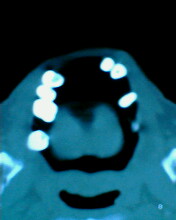

患者:男71岁,右侧上颚肿物无痛性生长7年.

右上颌骨近中线部见类圆形低密度区,上方见一液平,周围见一薄硬化环,前下方见一牙根,后方累及水平板。上方突入鼻腔前下部,下方突入口腔。

考虑:右侧上颌骨囊肿伴感染。